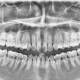

Pasien perempuan usia 25 tahun datang dengan keluhan mulut sulit terbuka dan terasa nyeri sejak 2 hari terakhir. Setelah dilakukan rontgen gigi ditemukan gambaran ini. Menurut dokter, apa yang dapat terjadi kepada pasien?

Dari pemahaman saya sebagai dokter umum, gigi pasien terjadi impaksi di gigi 48,

Betul sekali 48 impaksi dan karies, kondisi itu bisa menyebabkan trismus/susah membuka mulut ( normalnya buka mulut itu 3 jari ( jari telunjuk, jari tengah, jari manis bisa masuk dlm mulut pas posisi buka mulut). Kondisi hanya impaksi saja bisa menyebabkan trismus, apalagi ini ditambah karies. Sebaiknya periksa ke spesialis bedah mulut untuk penanganan lebih lajut ( dilakukan OD ), untuk mengatasi trismusnya. Semoga bisa membantu menjawab, terima kasih

tampak nekrosis pulpa

rekomendasi utk dilakukan odontektomi utk mencegah infeksi dan nyeri